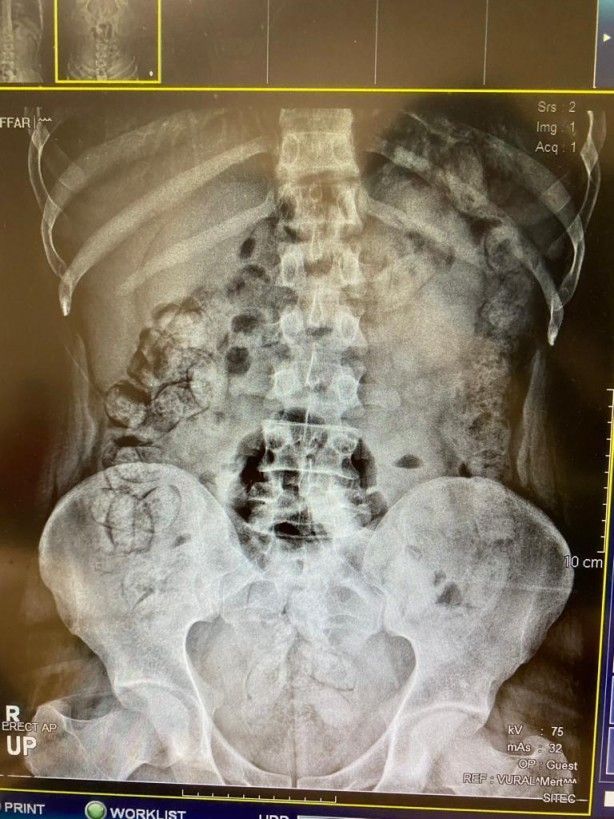

Çekilen röntgen filmlerinde şüphelilerin vücutlarında 62 kapsül eroin ve 210 kapsül afyon sakızı olduğu tespit edildi.

Röntgen çekimlerinde uyuşturucu kapsüllerinin şüphelilerin neredeyse iç organlarının her tarafına yayıldığı belirlendi. Doktor ve polis, vücutta tek seferde bu kadar yüklü miktarda uyuşturucu görmenin şaşkınlığını yaşadı. Gözetim altına alınan ve röntgenleri çekilen şüphelilerin vücudundan parça parça dışkılama yöntemi ile uyuşturucular çıkarıldı. Zanlıların hastanedeki işlemleri sürerken Narkotik Suçlarla Mücadele Şubesi ekiplerinin teknik ve fiziki takiplerinde, benzeri yöntemle yine aynı güzergahtan uyuşturucu götürüleceği bilgisi alındı. Bunun üzerine uygulama noktasında durdurulan bir otobüste, koltukta oturma şekilleri ile hal ve hareketlerinden şüphelenilen İran uyruklu Masoud T. ve Soleman O. gözaltına alınıp hastaneye götürüldü.